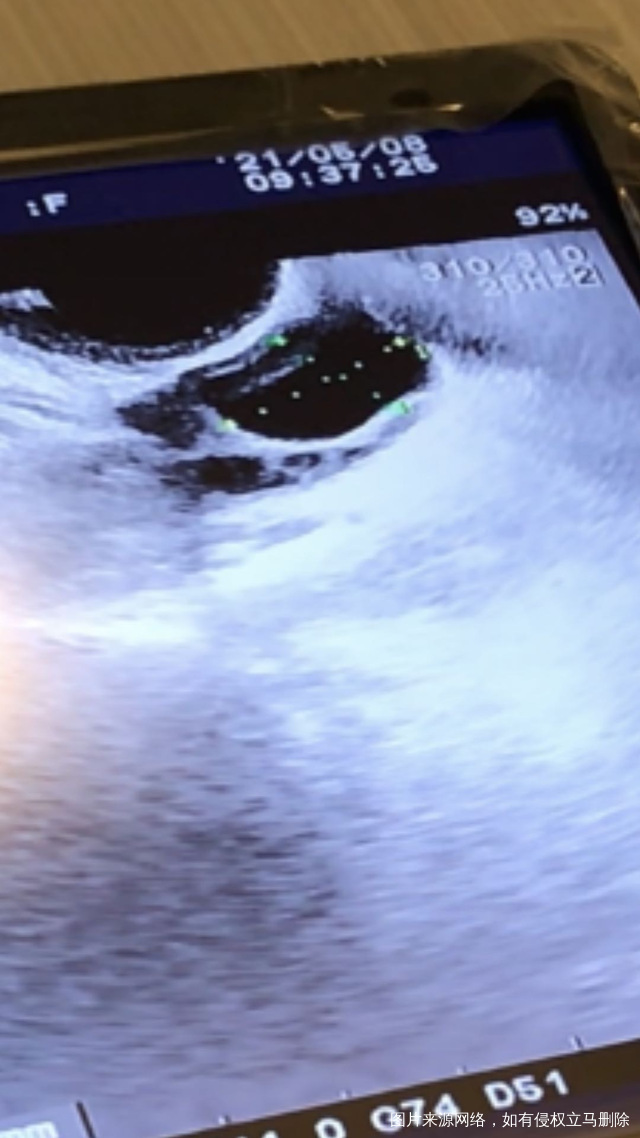

请医生帮忙看下b超图,卵泡20.7乘以14.5,内膜9.1,阴性,这个卵泡看起来张力不够是吗?这是感觉正在排卵还是马上要排了?还是卵泡长的不行?现在打破卵针是否合适?